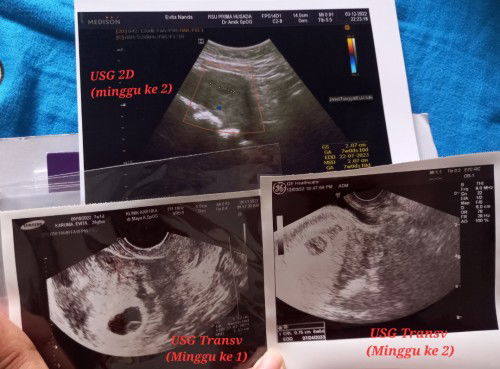

Hai bunda semua semoga kehamilannya diberikan kesehatan selalu yaa. Aku hpht 9 okt, ditanggal 12 nov pertama kali flek seperti difoto yg ke 2. Jalan seminggu aku kira itu haid. Tapi kok lama sekali keluarnya sampe tgl 27 nov fleknya. Akhirnya aku testpack ditgl 27 nov. Di tanggal 28 kuputuskan untuk usg transvagina diklinik spog. Itu hasilnya diminggu pertama terlihat sudah ada kantung dan isinya. Tapi dokter blm jelasin soal djj. Akhirnya disuruh bedrest total seminggu krn sebelumnya aku kerja sbg Desain Grafis. Dengan diberi resep dokter vitamin D, asam folat, dan Microgest 200mg dimasukkan lewat vagina 1x sehari. Selama proses bedrest flek mulai berkurang seperti gambar nomor 3, dihari terkahir bedrest tgl 3 Des, pagi dan sore aku buat jalan ringan di teras rumah. Dan coba duduk dikursi. Eh pas mau mau wudhu aku lihat flek keluar lagi sebanyak gambar nomor 2. Akhirnya malam itu aku putuskan langsung ke dokter spog tapi coba didokter yg berbeda diklinik yg beda juga. Disitu aku di usg 2D hasil tidak begitu jelas, entah dokternya pengambilan gambarnya tidak pas atau bagaimana ya. Lalu krn kurang yakin akhirnya di USG transv dan dokter bilang blm ada djj, padahal diumur 6-7 minggu kehamilan itu harusnya sudah ada. Dan beliau menjelaskan, klo janin tidak berkembang dengan baik. Dan pada akhirnya nanti harus dikuret, tapi dokter menyarankan krn obat penguatku belum habis jadi dihabiskan terlebih dahulu dan sambil dilihat perkembangannya bagaimana sampai USG selanjutnya ditanggal 12 Desember. Huhu Sedih dan pasrah saat ini rasanya :( ada yg punya pengalaman yang sama disini? 😭😭 Menurut bunda sekalian enaknya USG selanjutnya didokter yg Pertama atau yg Kedua ya? Aku bimbang ini :( #bantusharing #firstmom #firstbaby